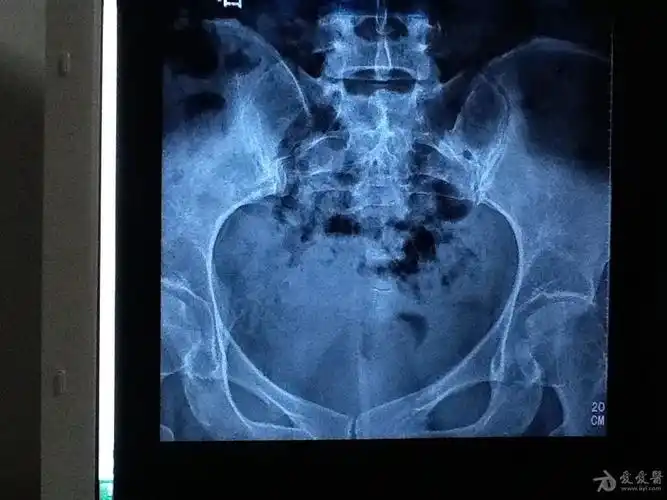

【读片】骶尾椎ct [病例帖]

尾椎骨骨折

尾椎骨错位

尾骨脱位图片